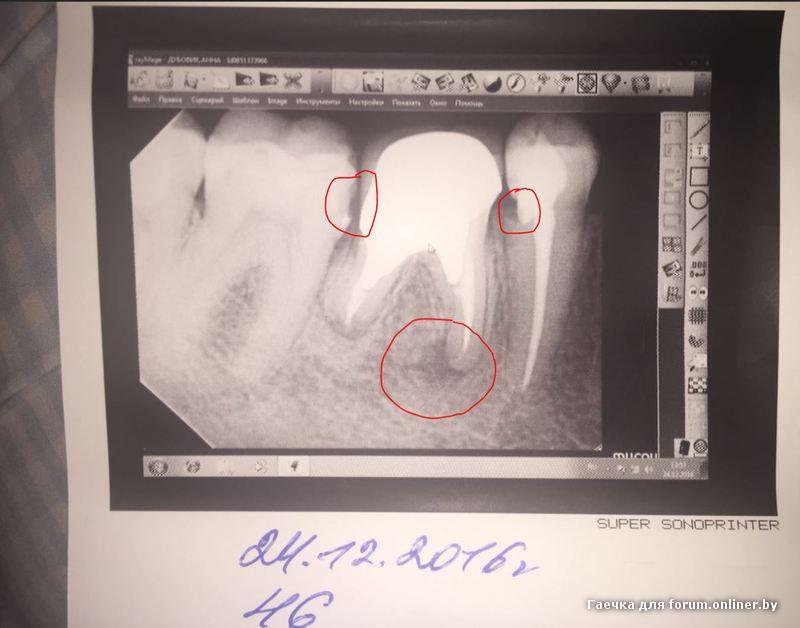

Здравствуйте! 4 дня назад заболел мертвый зуб под коронкой. Очень больно на него кусать в передней части (ближе к пятерке). Пошла к хирургу, сделала снимок. На корне образование. Решили, что удалить всегда можно и мне выписали Доксициклин и солевые полоскания. К сожалению, это совсем не помогло, всё равно болит, кусать невозможно и спать невозможно. Записалась на вторник на удаление. Зуб 46. У меня такой вопрос: если я его удалю, то как скоро можно будет поставить имплант? Сразу или ждать какое-то время. Хотелось бы сразу, но хирург у которой я буду удалять зуб имплантами не занимается. Можно ли удалить у нее (очень хороший специалист, вся моя семья ходит к ней), а потом идти к другому врачу на установку импланта в ближайшее время? Заранее спасибо за ответ.

P.S. на всякий случай фото

Гаечка:

Через 3-4 месяца.

А что лечить 5ку не сказала?